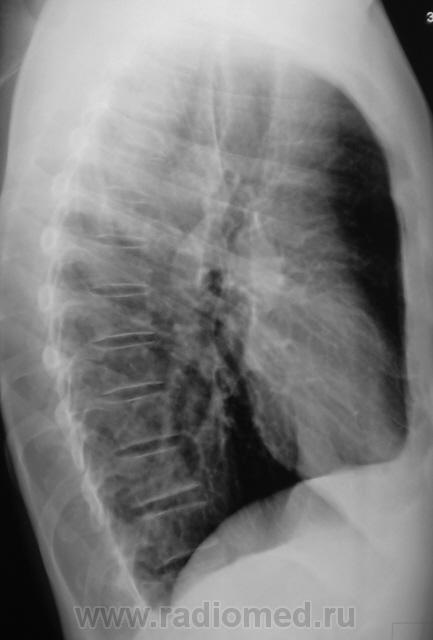

Еще контроль через 1 месяц.

Распад был изначально, но, к счастью больного, все закончилось практическим выздоровлением.

Долго что-то пневмонию лечили. А распад очень сомнительный. Больше на игру теней похож.

Да, лечение весьма затянулось.